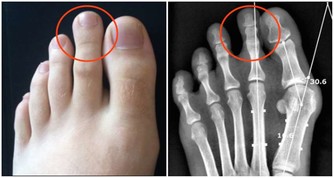

確診頸椎病並不困難,只要照一張X光片就可以了。

總 之,手麻症狀的確診,還需參考頸椎片、肌電圖等輔助檢查才能明確診斷。